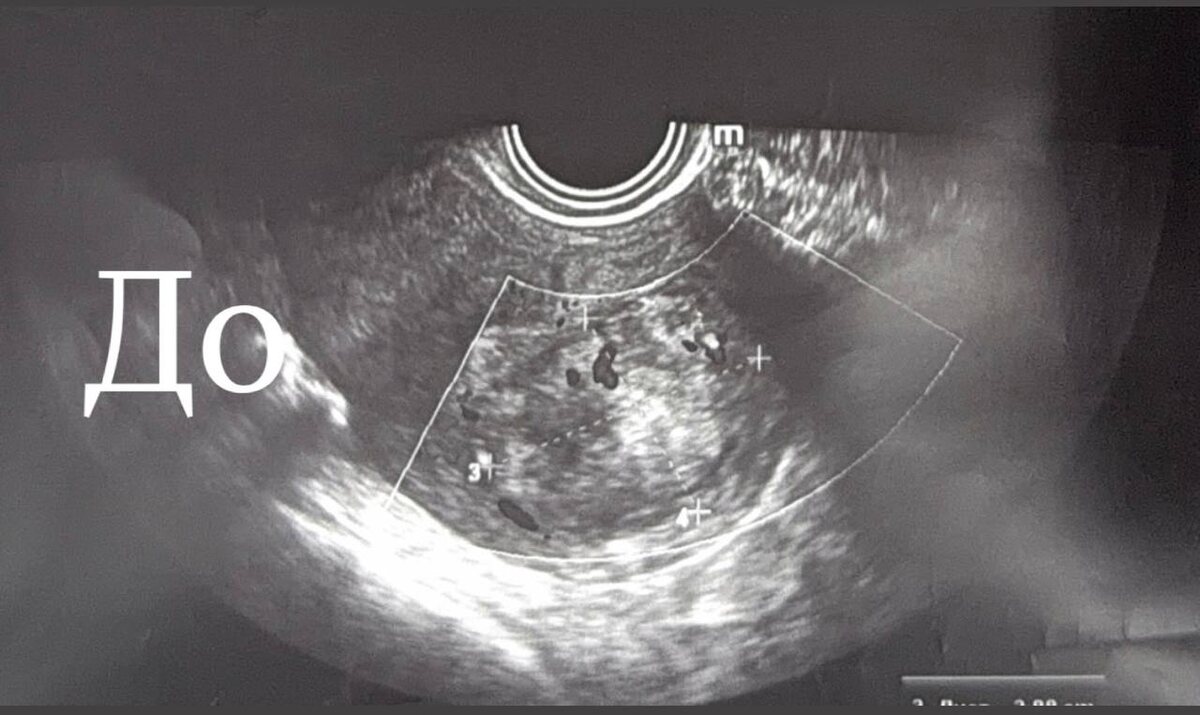

Случай 2025 года: пациентка, планирующая первую беременность, и сложный узел с нарушением питания. Из-за размытых границ опухоли мы не стали рисковать и провели лечение в два этапа с интервалом в 3 месяца. Методом гистерорезектоскопии, шаг за шагом, мы освободили полость матки.

Гистология: фибролейомиома.